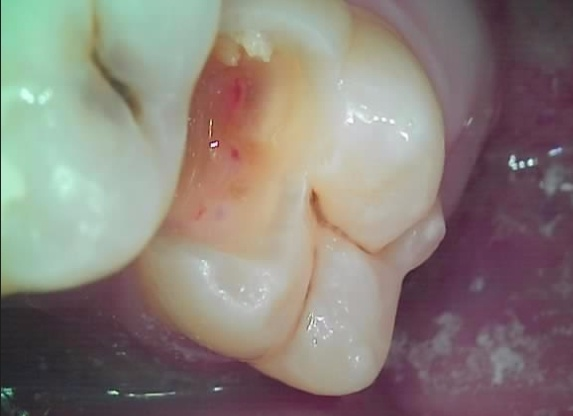

모든 충치를 제거하는 과정 중 신경이 노출되어서 (치아의 빨간 부위)

결국 신경치료를 할 수 밖에 없게 되었습니다.